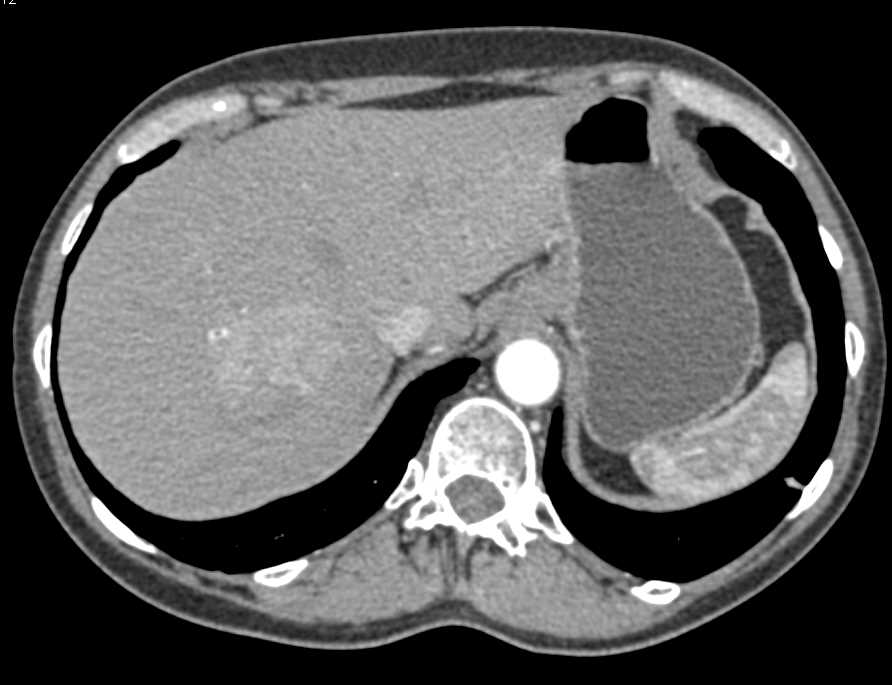

Zollinger-Ellison Syndrome with Thickened Gastric Folds and Liver Metastases